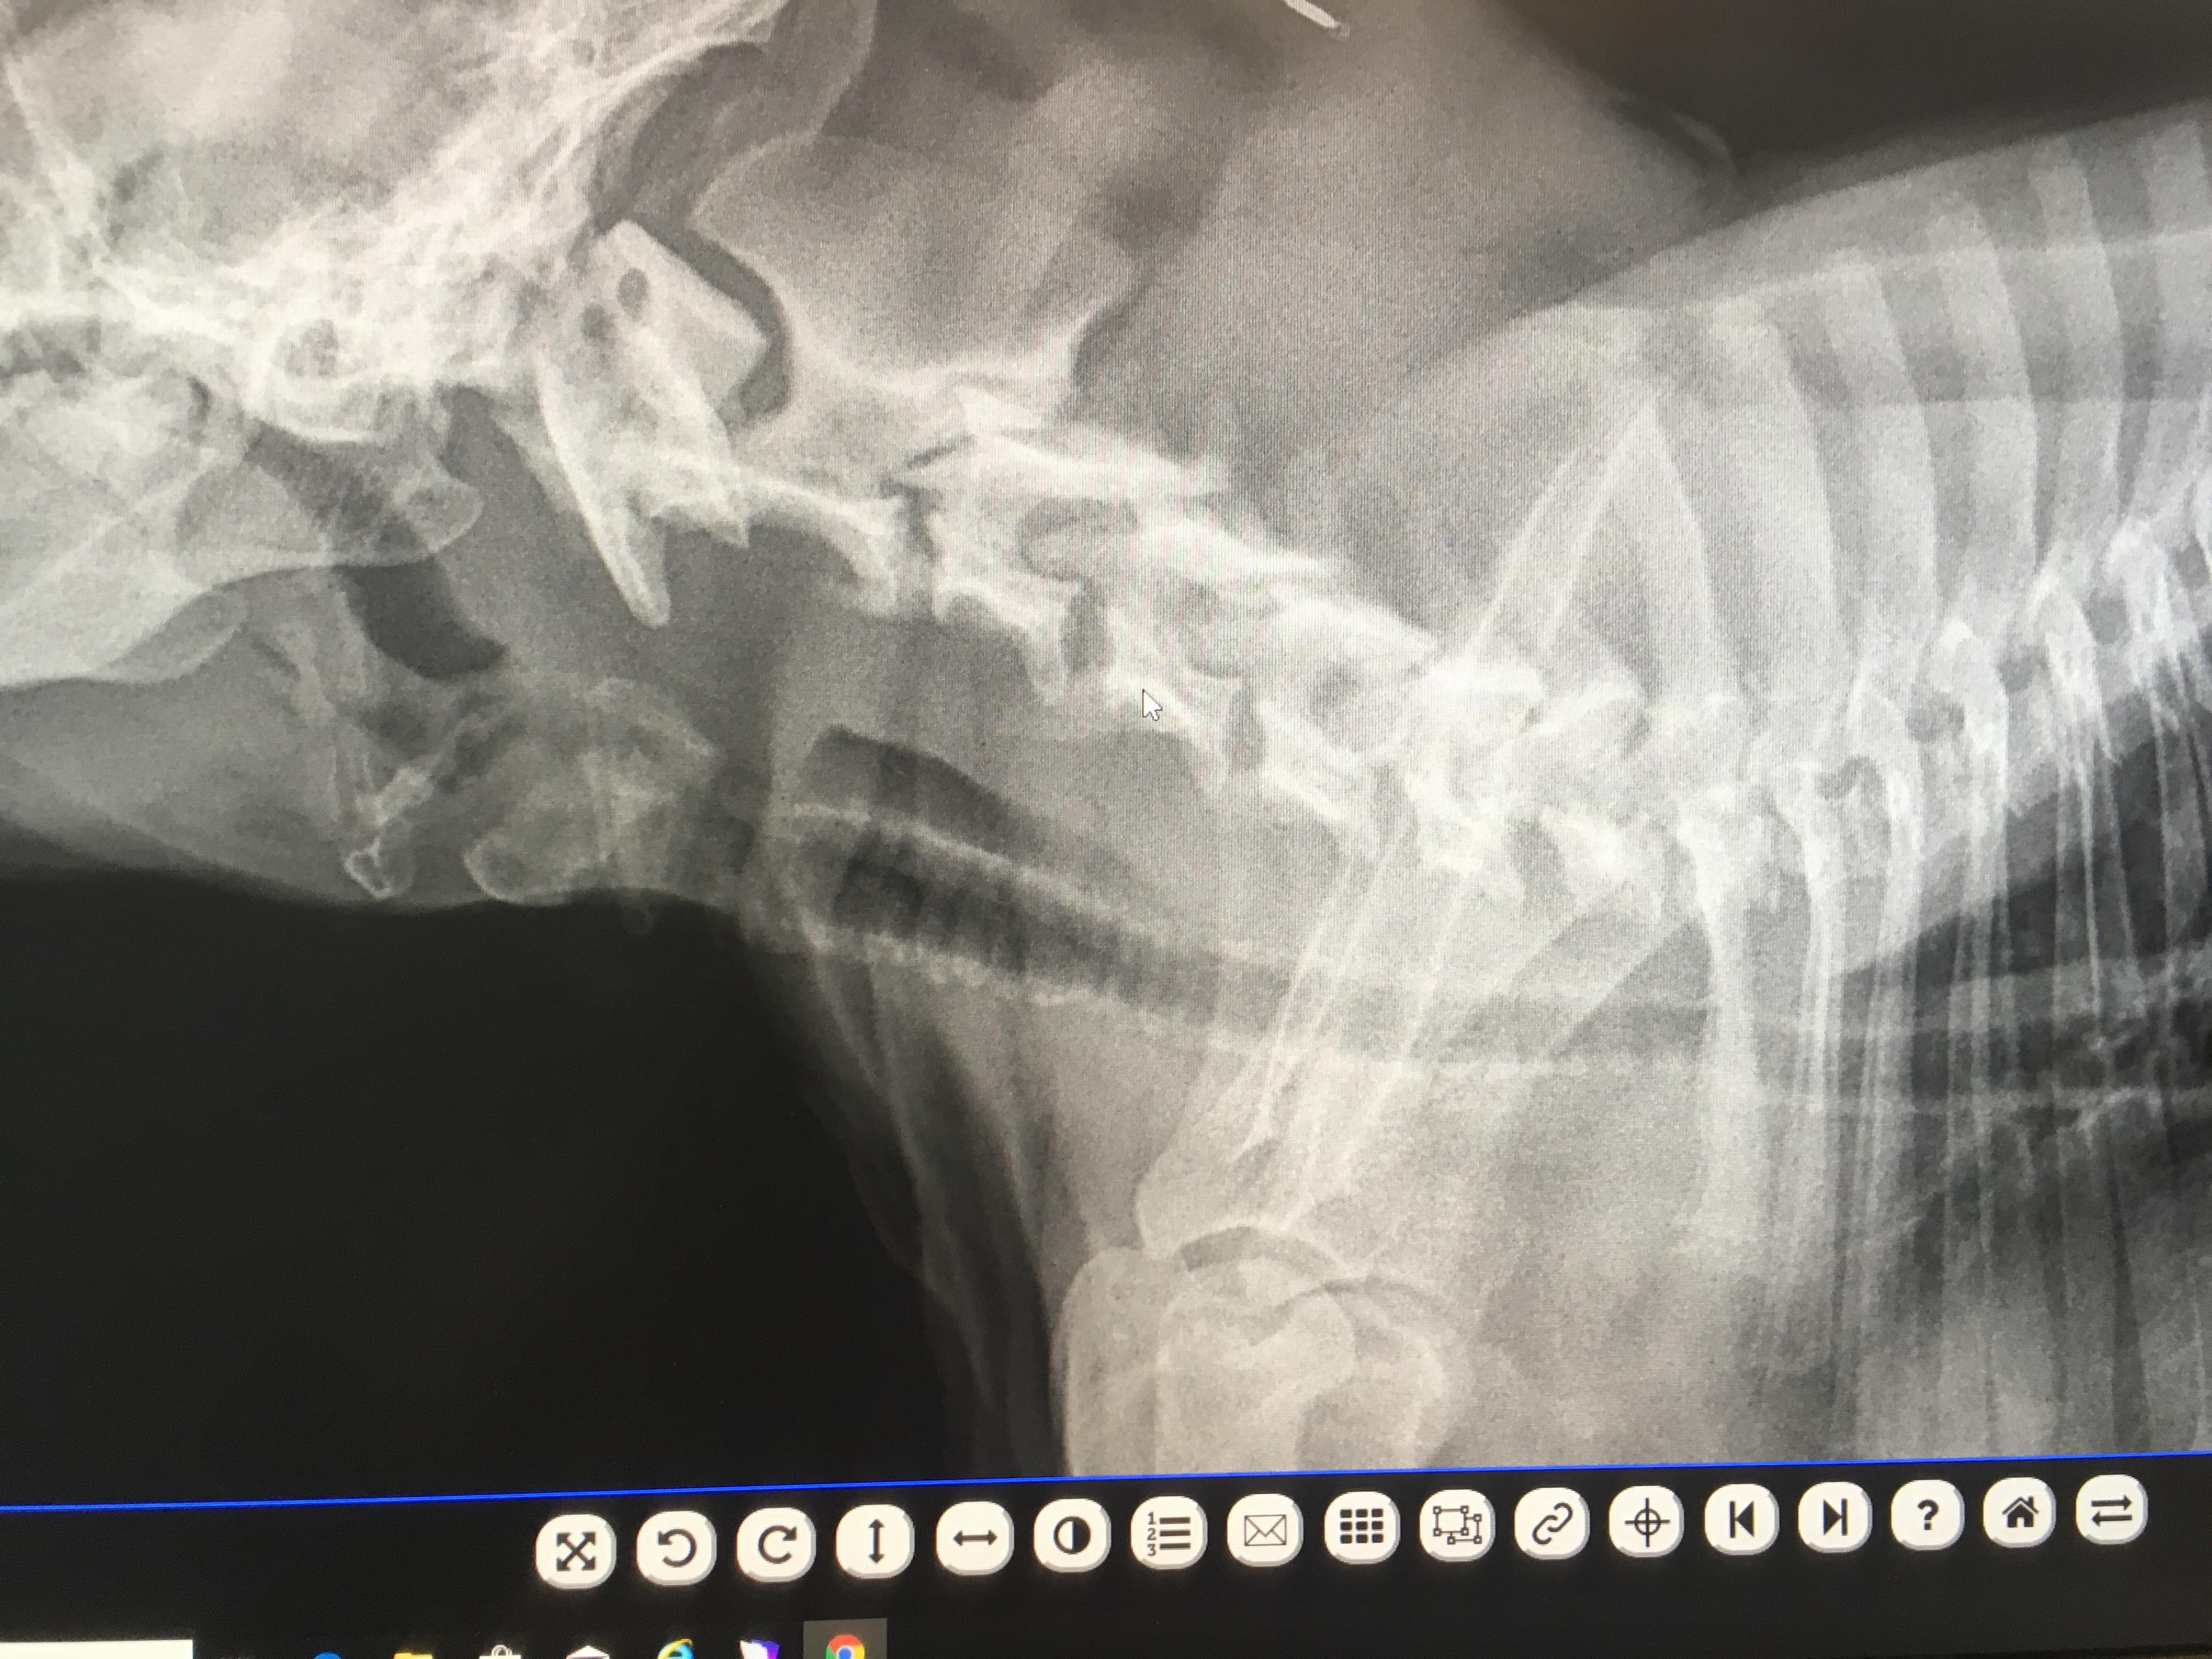

I have a 1 y/o american bully (pocket). We have had him since he was 8 wks old. Always has had labored breathing, but just attributed it to his short snout. Recently took him to a specialist due to his labored breathing appears to be getting worse. X-rays revealed tracheal narrowing with mineralizations. They said his tracheal flaps aren’t moving in their own and they want to permanently suture one flap open. Is this a common surgery? Also what could be the cause of this mineralization?

Yes, this is a pretty common surgery called a "tie back". I suggest you have it done if the specialist has recommended it. The mineralization is nothing to be concerned about - it is a very common finding although usually in older dogs. No one is quite sure why the body deposits the minerals in the tissue although it is suspected to be due to inflammation.